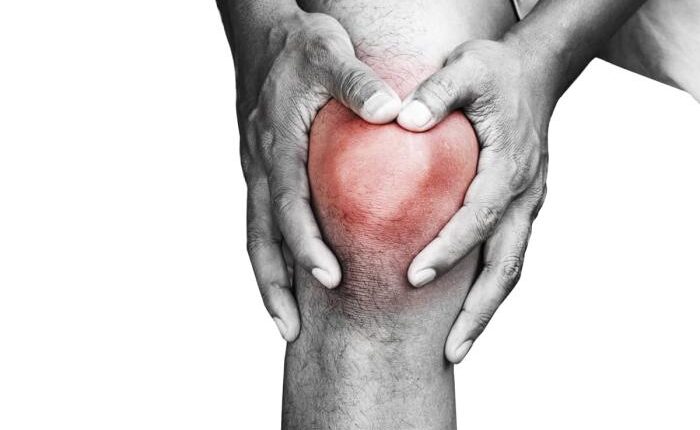

درمان زانو درد (راه حلهای قطعی، سریع بدون جراحی + علت و انواع درد زانو)_به رنگ صبح

نوشته و ویرایش شده توسط مجله به رنگ صبح زانو درد یکی از عارضههایی است که در دنیای امروزی و…